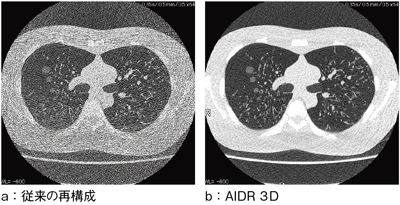

Adaptive Iterative Dose Reduction 3D(AIDR 3D)は,東芝の新しい画像再構成法である。再構成処理の中でScanner Model, Statistical Modelを用いた生データ空間でのノイズ低減処理と,Anatomical Modelを用いた画像空間でのノイズ低減処理を併用することで,従来よりも,最大50%のSD改善および75%相当の被ばく線量低減を実現した(図6)。また,投影データの検出器カウントが不均一な場合に発生するストリークアーチファクトも低減することができる(図7)。

図8に,ノイズ特性を示した。AIDR 3Dは,特に低線量データに対するSD改善率が高いことがわかる。実測した再構成時間は,34flame/s〔0.5mm×80列/0.35s/rot/HP 111/FC13/AIDR 3D(Strong)〕であり,臨床現場でストレスなく活用できる。さらに,AIDR 3Dは適用部位に制限がなく,心電図同期やVolume EC(Auto Exposure Control)との連動も可能である。追加ユニットは不要であり,東芝CTのAquilion PRIME,Aquilion CXL Edition,Aquilion RXL Edition,Alexion,Alexion Access Editionに標準搭載されている。

図7 AIDR 3D効果比較(模擬結節入り胸部ファントム)

120kV/10mA(3.5mAs)/0.35s/rot/BP 1.391/0.5mm×64

(画像ご提供:慶應義塾大学病院様)